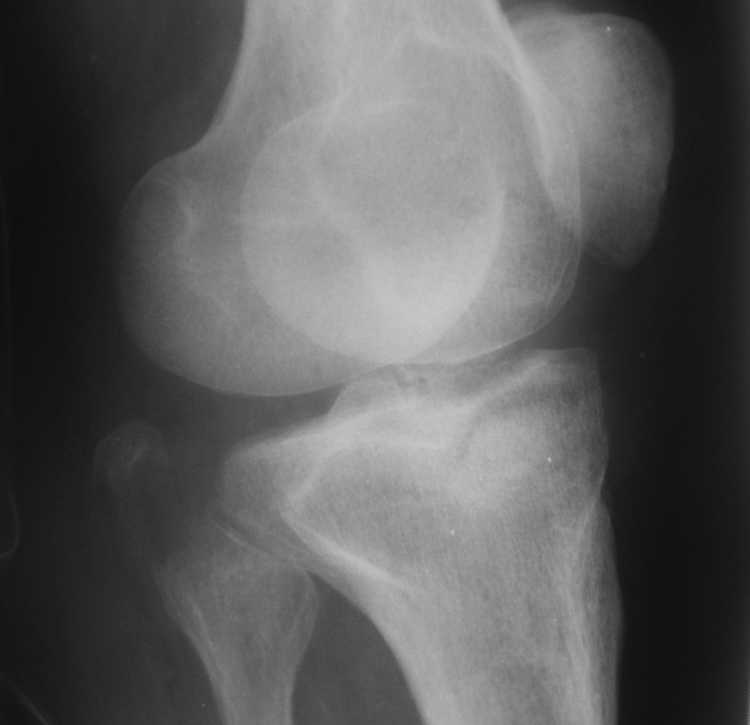

Высылаю рентгенограммы

1 совсем не уверен, что авульсию латеральной коллатеральной связкис маленьким фрагментом головки малоберцовой Вам удастся зафиксировать винтом или проволкой. Будьте готовы к другим методам фиксации или реконструкции связочного аппарата

2 если медиальный мыщелок - чистая импакция, без среза ( похоже на то по снимкам) - пластина, в общем-то, не нужна, достаточно "поднять" суставную поверхность, трансплантат ( совсем не обязательно аутотрансплантат - вполне подойдет автоклавированная чья-то головка бедра) и поддержать суставную поверхность парой крупных шурупов.

3 если есть возможность - было бы очень здорово перед операцией сделать КТ - можете найти много чего неожиданного